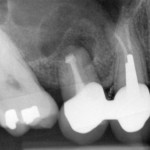

La rimozione dei perni endocanalari

La presenza di ostacoli fisici all'accesso ai canali è una complicazione importante nella messa in atto di un ritrattamento endodontico ortogrado. Un ostacolo che per definizione è proprio dell'elemento già trattato e si può pertanto incontrare solamente nel corso di un ritrattamento è rappresentato dalle ritenzioni endocanalari, principalmente i perni.